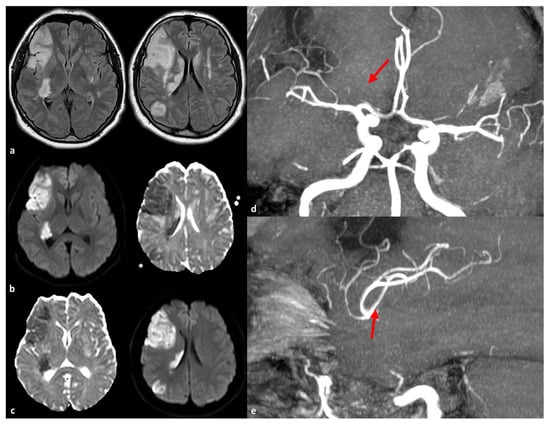

- Saito, S.; Hosoki, S.; Yamaguchi, E.; Ishiyama, H.; Abe, S.; Yoshimoto, T.; Tanaka, T.; Hattori, Y.; Liao, Y.C.; Lee, Y.C.; et al. Blended Phenotype of NOTCH3 and RNF213 Variants With Accelerated Large and Small Artery Crosstalk: A Case Report and Literature Review. Neurol. Genet. 2024, 10, e200176. [Google Scholar] [CrossRef]

| c.14576G > A | 29 | 124 | 384 | Japan | Carrier rate in CADASIL patients with intracranial stenosis: 23.5% (4/17) vs. 1.9% (2/107) without stenosis (p = 0.0032). Higher frequency of territorial infarction in carriers (75.0% vs. 20.0%, p = 0.0410). 2.6% of control population identified as carriers of the c.14576G > A variant. 21.9% of sporadic intracranial stenosis patients exhibited this variant in the Japanese population [5]. |

| c.14429G > A (p.Arg4810Lys) | 29 | 124 | 384 | Japan | Found in 4.8% (6/124) of CADASIL patients; higher than 1.5% in the general population. Present in 80–90% of familial moyamoya disease cases; significant risk factor for intracranial artery stenosis [12]. |